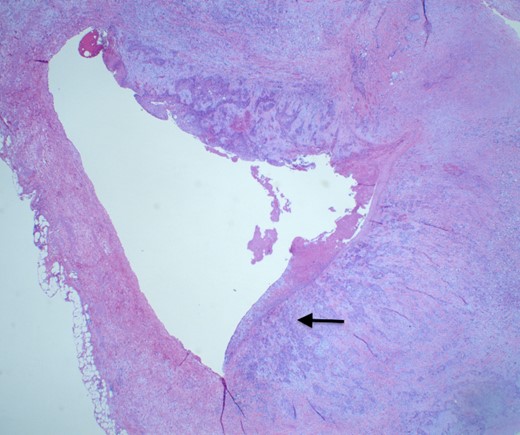

She underwent an open pylorus-preserving pancreatoduodenectomy with segmental superior mesenteric vein resection with primary reconstruction (ISGPS Type 3) without complication. Final pathology demonstrated a 3.6-cm poorly differentiated adenosquamous carcinoma with SMV invasion into the intima (Fig. 2), 1 of 24 regional lymph nodes with metastatic carcinoma, lymphovascular and perineural invasion (Fig. 3), and an 85% squamous differentiation (Fig. 4). There was a partial pathologic response (College of American Pathologist Grade 2) within the primary tumor and involved lymph node tumor [7]. There was noted to be tumor extension within 1 mm of the superior mesenteric artery margin (Fig. 5) (R1 status) with negative additional margins. She recovered without complications and was discharged home on the fourth post-operative day. Repeat staging CT imaging demonstrated no evident disease. She was initiated on adjuvant systemic therapy.

Adenosqumous carcinoma with both components (adeno and squamous) A19 Cytokeratin 7 immunostain, highlighting the adenocarcinoma, and p40 immunostain, highlighting the squamous carcinoma component